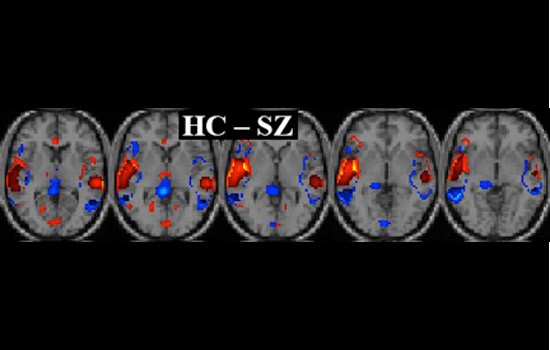

This series of images shows the difference between a healthy person’s brain versus a person with schizophrenia. The red areas on the brain template indicate the regions of a healthy brain involved in identifying and processing sounds while the blue areas indicate relatively more active regions of a schizophrenic brain. These images were obtained using Khullar’s image denoising technique in addition to other segmentation algorithms.

The fMRI scan captures the level of blood flow in the brain over time, similar to capturing a movie of the brain. Ordinarily the image sequence produced is extremely difficult to quantify. Khullar’s method identifies and quantifies regions of activity in the fMRI brain images in a way that allows clinicians to differentiate characteristics of healthy and schizophrenic patients.